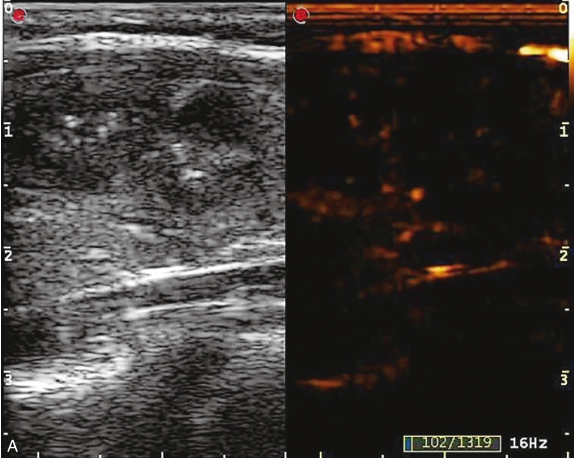

甲状腺右叶中部可见一个肿块,大小约为2.6cm×1.8cm×1.8cm,形状尚规则,边界尚清楚,内部为低回声,分布不均匀,后方回声无变化,CDFI显示肿块内可见丰富的血流信号,见图1-9-1。

图1-9-1 甲状腺髓样癌常规超声图像

A.甲状腺右叶低回声结节纵切面灰阶超声图像;B.甲状腺右叶低回声结节横切面灰阶超声图像;C.CDFI图像